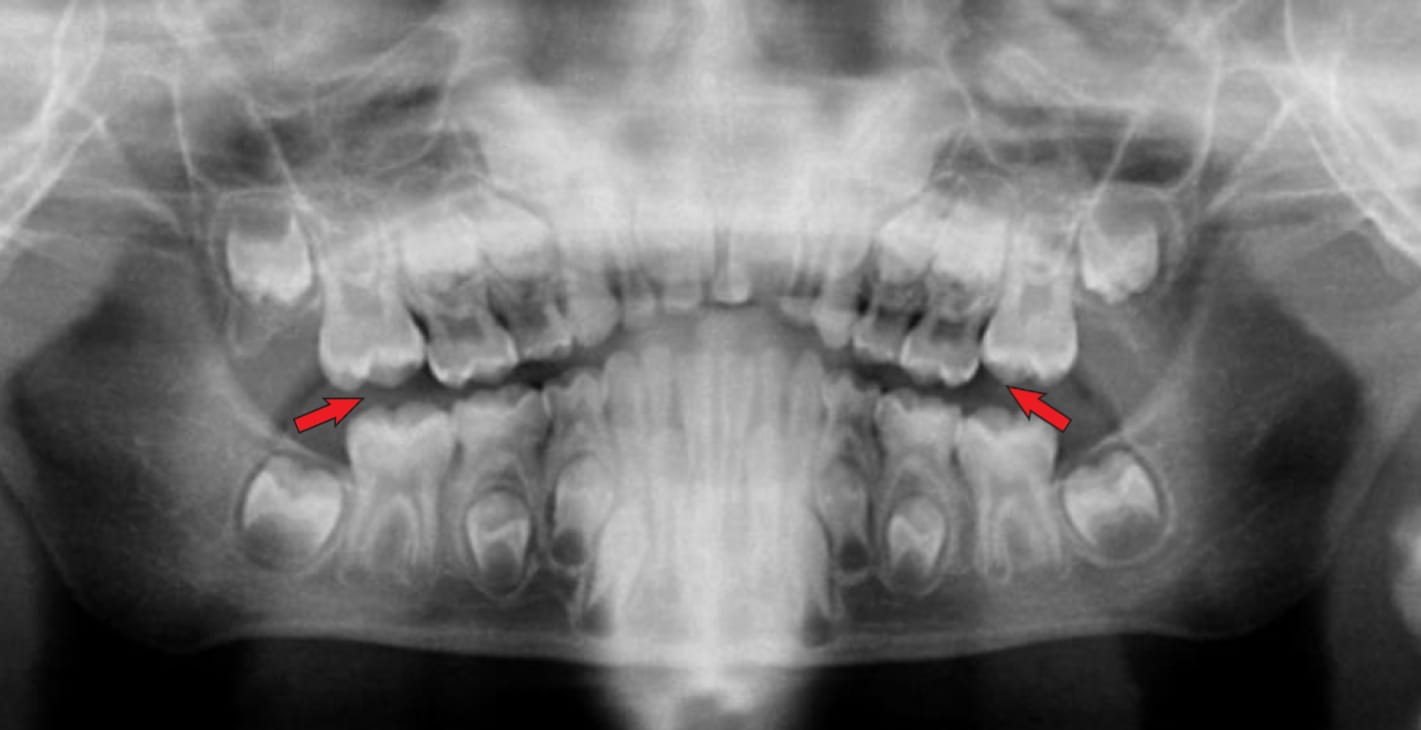

⚠️ Image fantôme

Une image fantôme consiste en un artefact radio-opaque qui apparaît dans une image panoramique et qui est causé par la double pénétration du faisceau de rayons X dans un objet. Cette image fantôme ressemble à l'image réelle, mais elle apparaît sur la face opposée du film, elle est plus grande et plus haute que l'image réelle, et elle est diffuse.

Solution : Demandez au patient de retirer tous les objets métalliques ou autres qui ne permettent pas aux rayons X de passer, tels que les lunettes, les boucles d'oreilles, piercings, colliers, prothèses amovibles, appareils orthodontiques amovibles, etc..

Image 1: Image fantôme